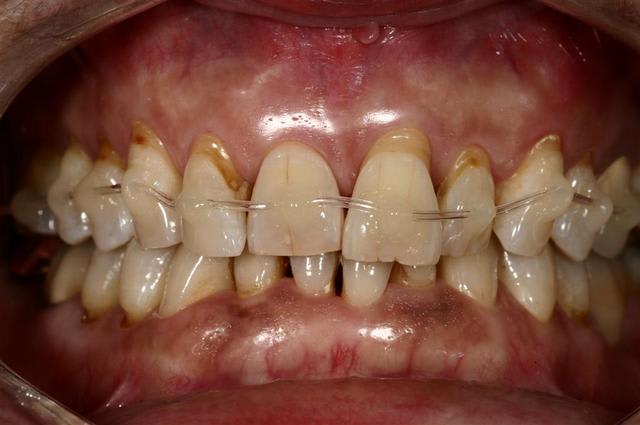

Envie d'améliorer le sourire... petit traitement d'alignement avec une technique simple et efficace à la portée de tous la preuve...

Tout d'abord, le but de mon intervention n'est pas de donner une leçon d'orthodontie, mais d'exposer une technique qui me semble accessible, peu honnéreuse et qui permet d'améliorer la prise en charge de mes patients.

En effet qui n'a jamais été devant une situation ou "un peu" d'orthodontie permettrait de faciliter la réalisation d'une prothèse, ou de corriger les effets d'une parodontite sur l'aligenement dentaire ?

Pourtant j'en ai fait des contentions...(Attelle or avec pins, cavalier, Ribbond, etc etc...)

Quelques photos jointes pour vous'assurer que je ne bluffe pas ;)